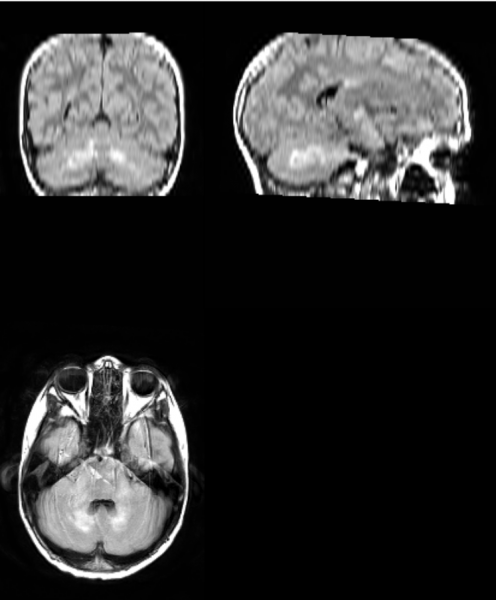

The best way to see many of the features of the disease is to do FLAIR imaging (a type of magnetic resonance imaging) on the brains of patients. In FLAIR images of neurofibromatosis 1 patients, there often are abnormally bright spots that likely indicate the presence of fluid between layers of myelin sheaths—the insulation surrounding certain nerve cells—which may contribute to the cognitive deficits observed in patients.

Unidentified Bright Objects—the bright spots in the FLAIR images—have been traditionally defined and segmented (digitally separated for further study) manually, which requires intensive training and is time-consuming and expensive. The current work, led by first author and neuroscience Ph.D. student Emily Harriott and co-author and recent neuroscience Ph.D. graduate Tin Nguyen, tested and validated a semi-automated approach for detecting and segmenting UBOs in children and adolescents with neurofibromatosis 1. Cutting lab staff researcher Laura Barquero also participated in the study.

The new approach, which uses a tool called the Lesion Segmentation Tool, reliably identified and segmented UBOs and was much faster than doing the work manually. After establishing the utility of LST, the scientists explored possible correlations between total UBO volume and cognitive function. The researchers demonstrated that total UBO volume was related to single word reading ability, phonological awareness (recognizing and manipulating spoken parts of speech) and visuospatial skills, and participants with greater UBO volumes had lower scores on these cognitive measures.